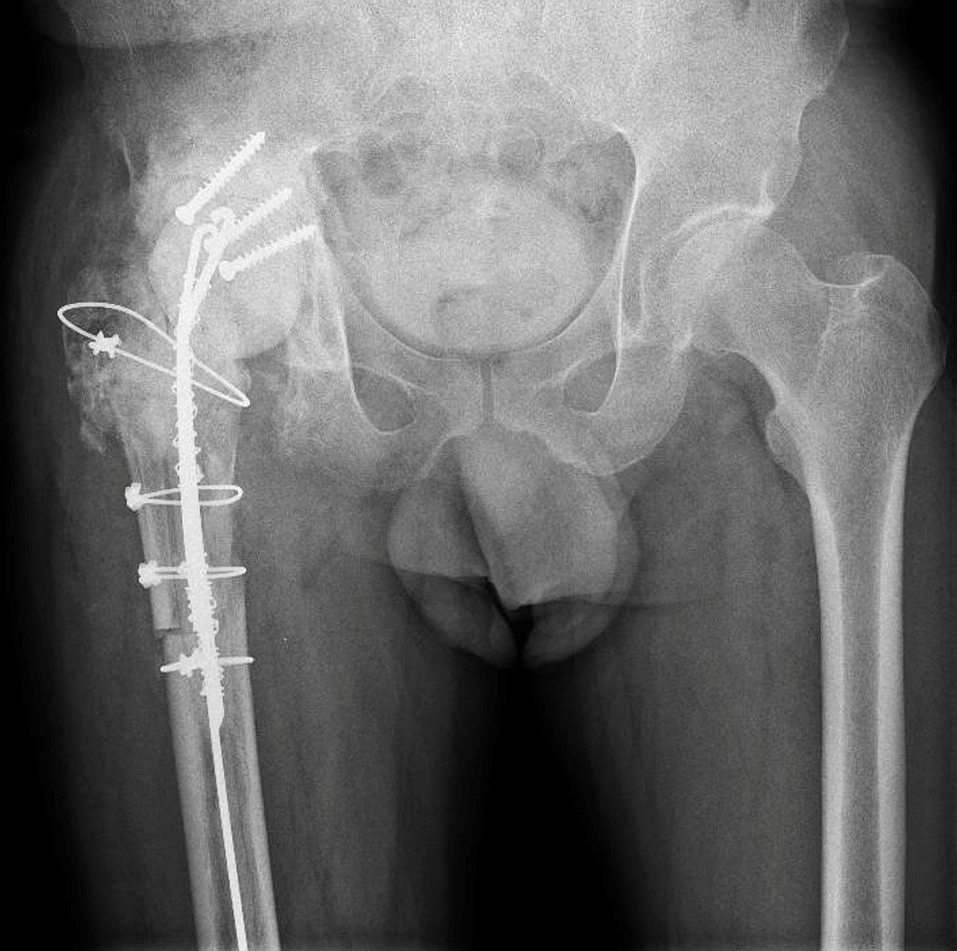

Preoperative X-ray demonstrating severe acetabular bone loss and loosening in a multiply revised right hip.

A 64-year-old male patient with arterial hypertension and no known drug allergies was referred with chronic PJI of the right hip

due to multidrug-resistant Pseudomonas aeruginosa.

His surgical history was complex. Thirty years earlier, he had sustained an acetabular fracture in a road traffic accident that had

been treated with osteosynthesis. This was followed by total hip arthroplasty for post-traumatic osteoarthritis and an early acetabular revision two years later. Subsequently, he developed a PJI that had already been treated with a two-stage exchange. Despite repeated debridements, the infection persisted.

At presentation, clinical examination revealed multiple lateral and posterolateral scars, a proximal fistula with seropurulent discharge, and severely restricted range of motion limited to 0–45° of flexion with absent rotations.

Plain radiographs demonstrated a loose acetabular component, severe acetabular bone loss, and heterotopic ossification.